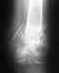

Такое положение было бы как-то приемлемо в ближайшие 2-3 недели после травмы. Почему в течение первого месяца не был выполнен переход с временной наружной фиксации на окончательную внутреннюю? Или хотя бы аппарат Илизарова?

Неизвестно, каково состояние мягких тканей поврежденного сегмента. Если явного нагноения зоны перелома нет, желательно бы организовать, пусть и запоздало, но замену наружного фиксатора на внутрикостный. Потребуется удалить обломки сломанных стержней. Лучше использовать интрамедуллярный штифт с антибактериальным покрытием.